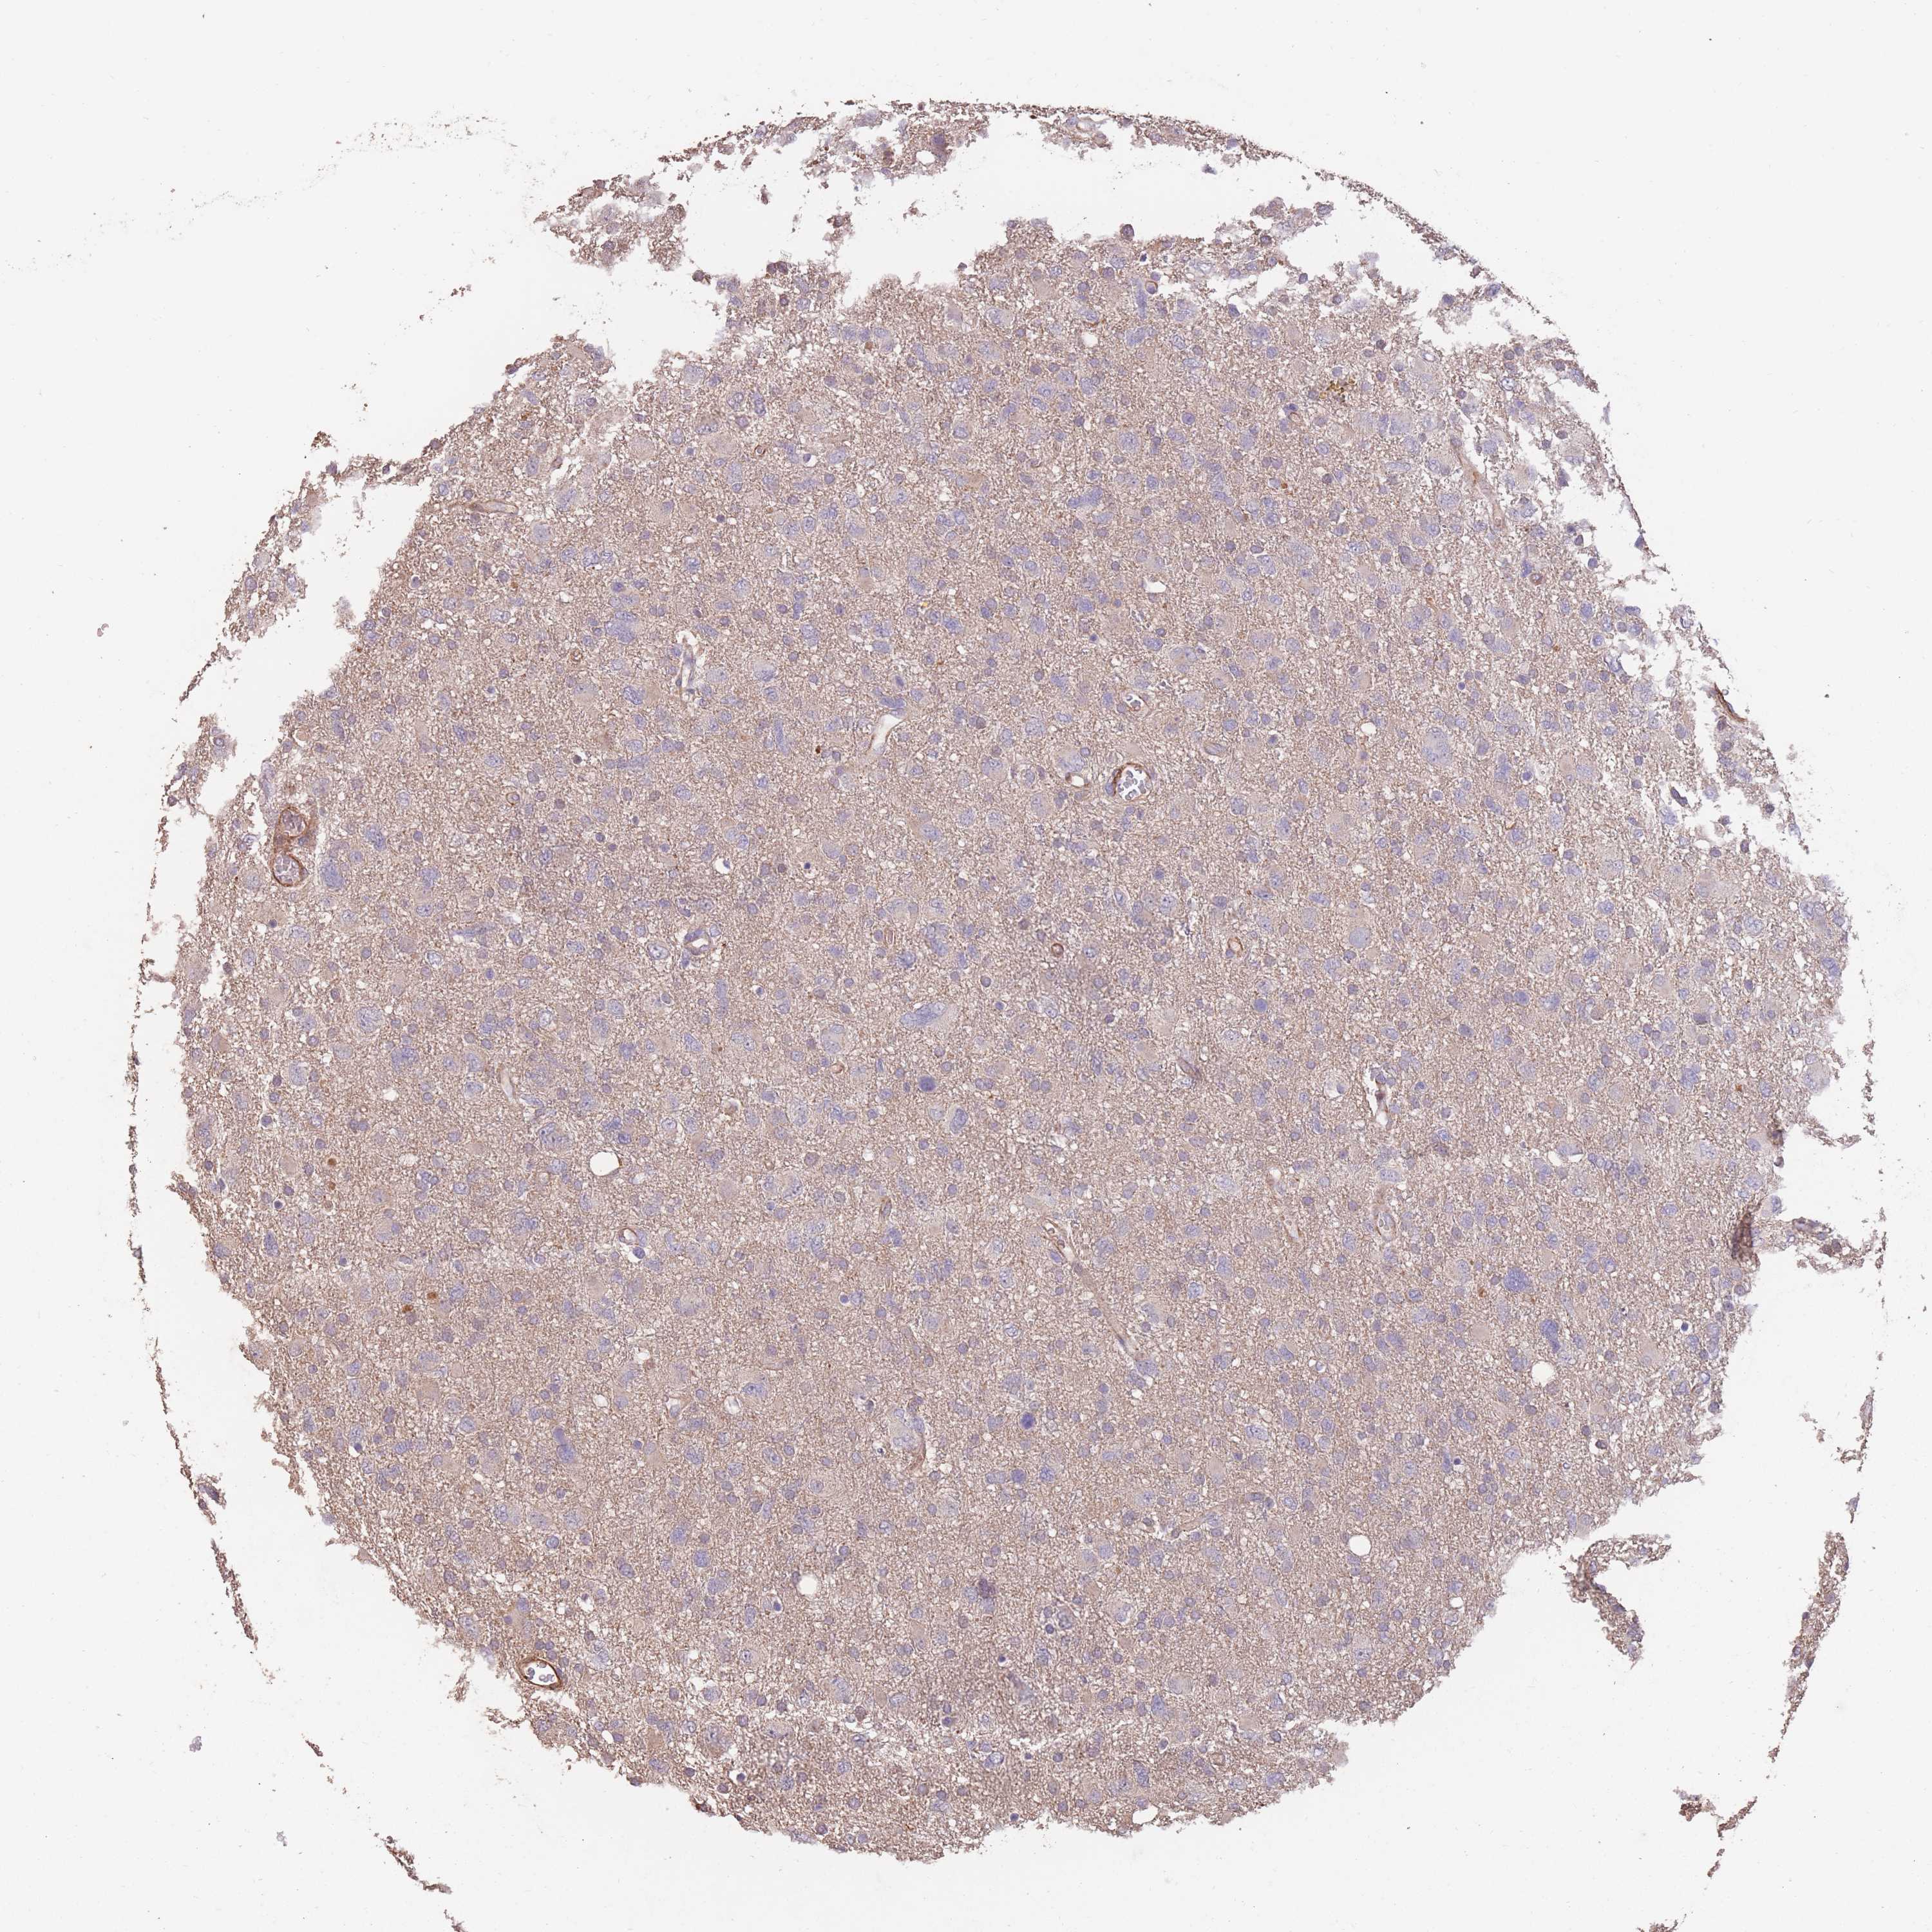

GLIOMA - Protein expressioni

A mouse-over function shows sample information and annotation data. Click on an image to view it in a full screen mode. Samples can be filtered based on level of antibody staining by selecting one or several of the following categories: high, medium, low and not detected. The assay and annotation is described here.

Note that samples used for immunohistochemistry by the Human Protein Atlas do not correspond to samples in the TCGA dataset.

Antibody stainingi

Antibody staining in the annotated cell types in the current human tissue is reported as not detected, low, medium, or high, based on conventional immunohistochemistry profiling in selected tissues. This score is based on the combination of the staining intensity and fraction of stained cells.

Each image is clickable and will lead to virtual microscopy that enables deeper exploration of all samples and also displays staining intensity scores, fraction scores and subcellular localization as well as patient and tissue information for each sample.

Antibody HPA006592

Staining

High

Medium

Low

Not detected

Intensity

Strong

Moderate

Weak

Negative

Quantity

>75%

75%-25%

<25%

None

Location

Nuclear

Cytoplasmic/membranous

Cytoplasmic/membranous,nuclear

Glioma, malignant, Low grade

Glioma, malignant, High grade